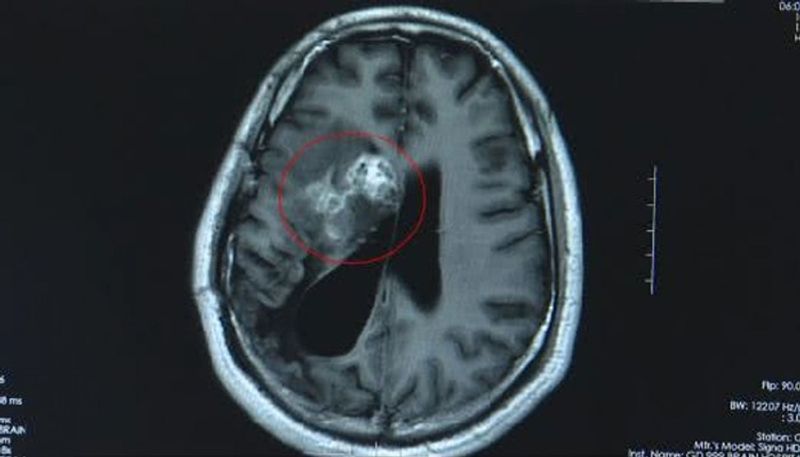

എന്നാല് 2018ഓടെയാണ് തലച്ചോറിനുളളിലെ പുഴുവിനെ ഡോക്ടര്മാര് കണ്ടെത്തിയത്. 12 സെന്റിമീറ്റര് നാളത്തിലുള്ള പുഴുവായിരുന്നു വാങിന്റെ തലയ്ക്കുള്ളില് ഉണ്ടായിരുന്നത്. മനുഷ്യ ശരീരത്തിനുള്ളില് ഇത്രയും വലിയ പുഴു ജീവിക്കുക അസ്വഭാവികമായ കാര്യമാണെന്ന് ഡോക്ടര്മാര് പറയുന്നു. രണ്ട് മണിക്കൂര് നീണ്ട ശസ്ത്രക്രിയയിലൂടെയാണ് പുഴുവിനെ പുറത്തെടുത്തത്.